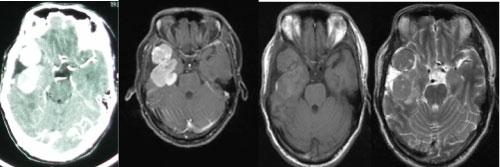

A 34-year-old man presented to hospital in 2006 with headache, tinnitus, intermittent nausea for one months. Cranial computed tomography (CT) demonstrated the right sphenoid ridge lesions (Figure 4), and underwent surgical excision of the right sphenoid ridge tumor under general anesthesia (Figure 5). Meningioma was diagnosed post surgically. In 2010, a following up computed tomography of the patient revealed a small recurrence of meningeal tumor and then treated with Gamma knife (Figure 6 and Figure 7).

7 years after the right sphenoid ridge meningioma surgery, the patient presented to us again with back pain for 2 months. The magnetic resonance imaging (MRI) and CT (2013) (Figure 8) showed the patient had a surgical scar at the right frontal temporal, a frontal temporal skull defects, and the tenderness and percussion pain on thoracic. The limb muscle strength was level 5, the bilateral limb skin' feeling was normal, the limb muscle tension was not high, and the bilateral Babinski, Brudzinski, and Klinefelter signs were negative. The CT, MRI and CTA examination showed the intracranial meningeal tumor recur again and metasted to vertebra thoracalis and vertebra lumbalis (Figure 9). Three surgery were taken for the recurrence and metastases of the meningeal tumor. Firstly, thoracic tumor resection and thoracic pedicle screw fixation were taken for the thoracic metastasis on general anesthesia (Figure 10) and then the second operation was perform for the resection of the recurrence of meningeal tumor; At last, the lumbar tumor resection and lumbar pedicle screw fixation were taken for the lumbar metastasis on general anesthesia (Figure 11) and the tumor was further diagnosed to be intracranial meningeal hemangiopericytoma.

Figure 8: The cranial CT test in 2013 (tumor recurred). View Figure 8